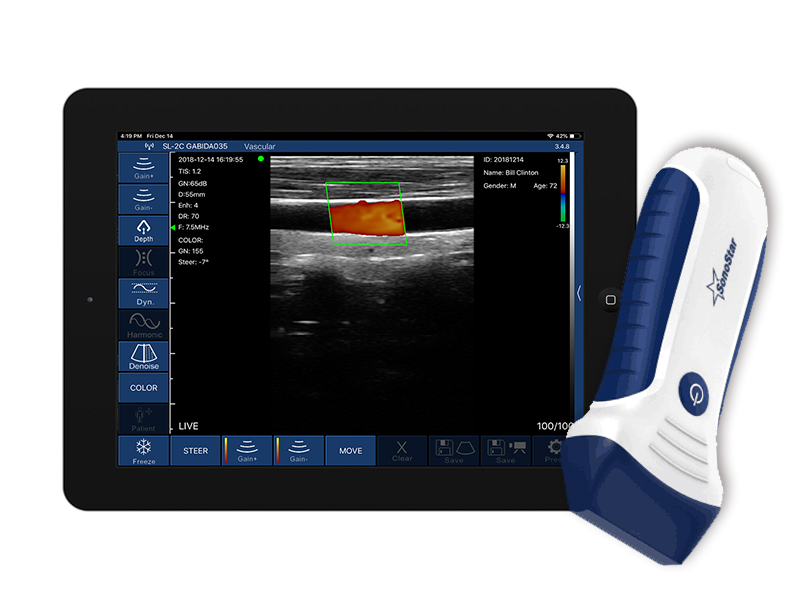

7L

DB7L(Plus系列,加厚电池)

DC7L(Plus系列,加厚电池)

• 扫描方式:电子阵列扫描

• 探头频率:7.5/10MHz

• 扫描深度:20-100mm,可调

• 显示模式:B、B/M、Color、PW、PDI

• 图像调节:增益、焦点、反相脉冲谐波、降噪

• 穿刺辅助功能:平面内穿刺引导线功能,平面外穿刺引导与血管自动测量功能

• 电池工作时间:常规型号1.5小时,加厚电池版本3小时,且可随时无线充电无限延长工作时间

• 充电方式:无线充电/有限充电

• 测量功能:距离、面积、周长、心率、产科

• 电影回放:手动和自动回放,可设置回放帧数为100/200/500/1000

• 图像/视频保存:jpg, png, mp4, DCM多种格式

• 探头与主机连接方式:wifi无线连接

• Wifi类型:802.11n/2.4G/5G双频450Mbps

• 图像帧频:18 f/s

• 软件支持系统:苹果iOS和安卓Android,Windows

• 尺寸:150mm×50mm×20mm

• 重量:200g